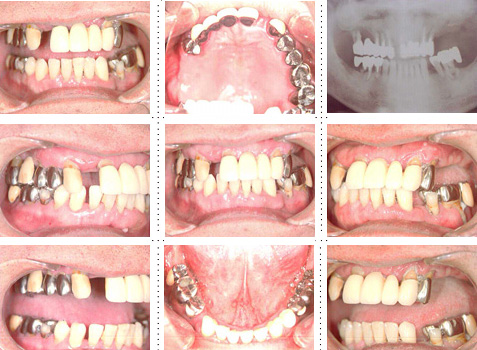

症例8

62才 男性

このようなケースは、残存歯を残すのか抜歯かの決断に迫られます。もし私の口腔内がこのケースだった場合、どの治療法を選択するのかをお話します。10年後、15年後を考慮し残存歯は全て抜歯し、上下顎共に8本ずつインプラントを埋入することにしました。

顎骨の質・量ともに十分でインプラント埋入は簡単です。ブリッジを製作する時の咬み合わせが一番問題となり、仮歯の段階で十分に咬合を安定させ、ブリッジ製作には技工士との連携が必要となります。今までこの様なインプラントのフルブリッジをセット後、インプラントが抜けた事は1度もありませ ん。